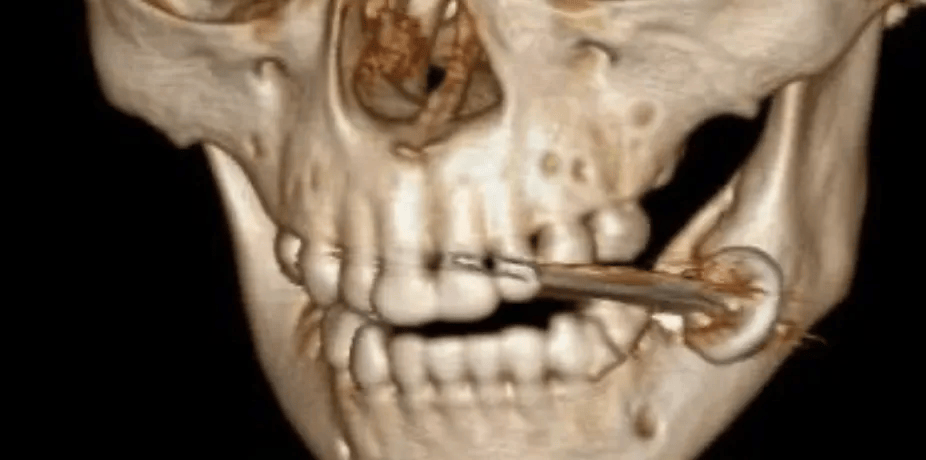

近日,云南大理一名2岁幼儿萌萌(化名) 因好奇将电池放在嘴里咬,导致电池爆炸,电池的保护盖和集电器卡在咬肌和颊肌之间怎么注册皇冠信用網。经紧急送医救治,目前,孩子无生命危险,已在口腔颌面外科接受手术后进行康复治疗。

急诊科医生发现萌萌嘴里含着烧糊的柱状物体, 隐约可见嘴里血肉模糊,还有个“血洞”怎么注册皇冠信用網。急诊科请口腔颌面外科会诊后,监测患儿生命体征,迅速开通绿色通道。

通过完善检查,口腔颌面外科值班医生发现电池的保护盖和集电器卡在萌萌的咬肌和颊肌之间怎么注册皇冠信用網。

口腔颌面外科值班医生立即联系麻醉科安排急诊手术,在萌萌入院1小时内为他施行了“口腔爆炸伤清创术+异物取出术”怎么注册皇冠信用網。电池的爆炸伤局限在口腔软组织多处穿孔, 幸运的是,萌萌没将电池碎片吞下肚。

经过探查,医生将电池保护盖、集电器及残留碎屑完整取出,妥善止血,清理创口并对位缝合,快速解决了这个危机怎么注册皇冠信用網。